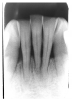

Figure 1 is a molar bitewing radiographic image that discloses a defective abutment restoration on tooth #4. The restoration ends short leaving open margins.

Figure 1 - Defective Restoration; Abutment Tooth #4

Figure 1